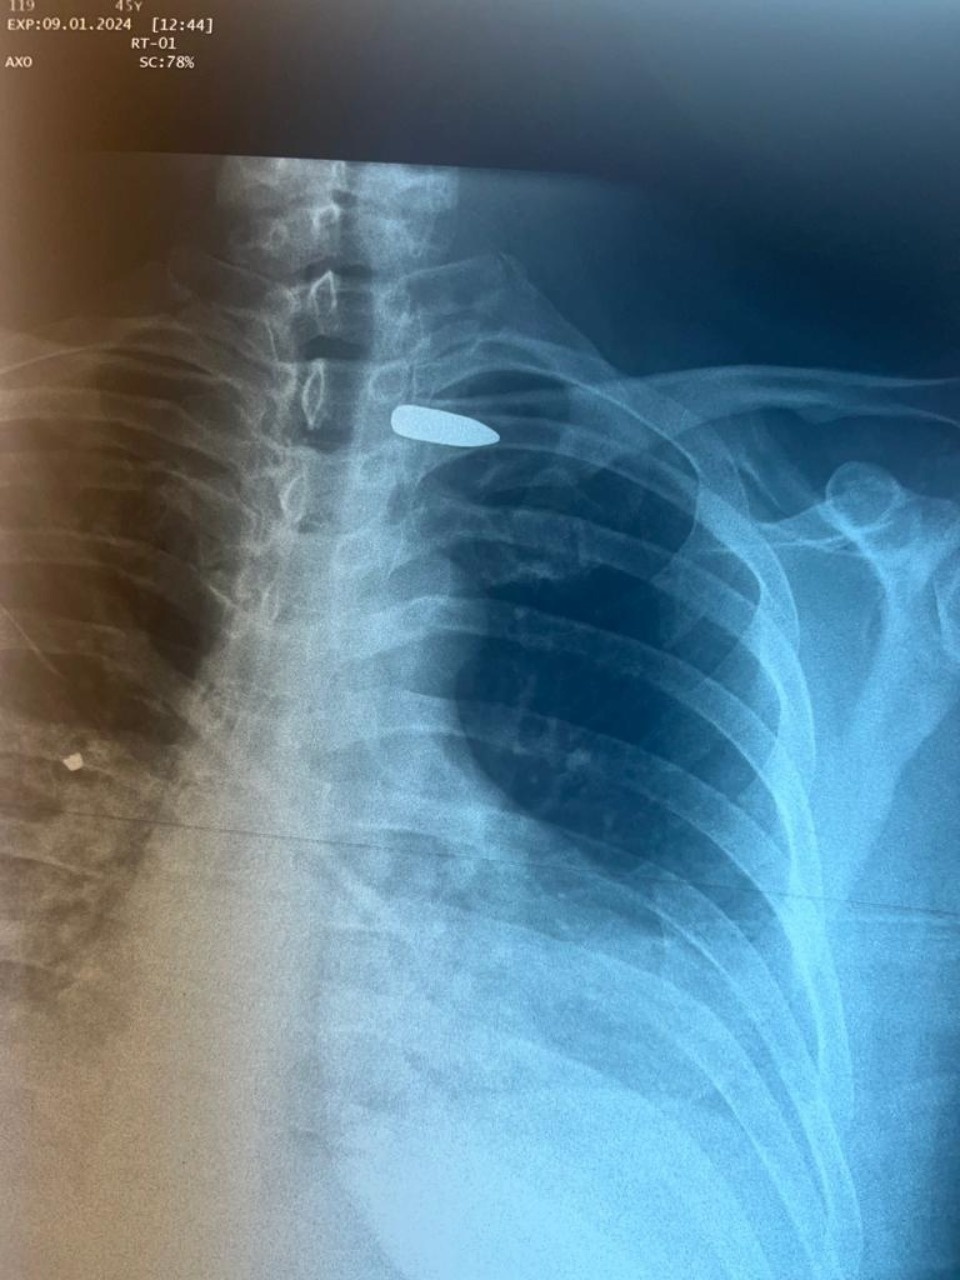

«Вследствие проникающего ранения в правую половину шеи пуля осталась в области сосудисто-нервного пучка в подключичной области слева», – рассказали в больнице и отметили, что мужчине потребовалась операция, в которой участвовал сосудистый хирург Абдулло Шабонов.

Пулю, находящуюся между ключицей и подключичными сосудами, извлекли. На данный момент состояние пациента оценивается как удовлетворительное.